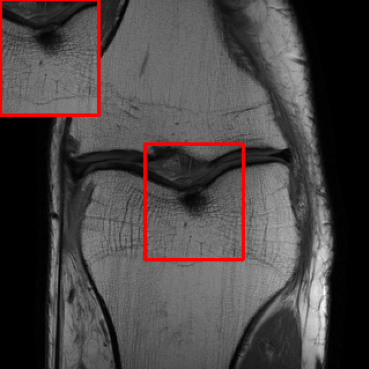

Performance on the Stanford FSE Dataset: We also performed image reconstructions with the Stanford multi-coil FSE dataset, which is a smaller dataset. We used same settings for the networks and training as in Section IV-A. Table III shows that LONDN-MRI significantly outperforms the globally learned MoDL network at both 4x and 8x acceleration. This indicates benefits for the proposed framework for smaller, more diverse datasets. Figs. 7 and 8 display visual comparisons that show the LONDN-MRI scheme recovering sharper features than the globally learned network.

| Ground Truth | Initial | Global | LONDN-MRI | LONDN-MRI | Oracle |

| (1 iteration) | (2 iterations) | ||||

![]() |

| PSNR = dB | PSNR = 22.01 dB | PSNR = 29.02 dB | PSNR = 31.46 dB | PSNR = 31.74 dB | PSNR = 31.87 dB |